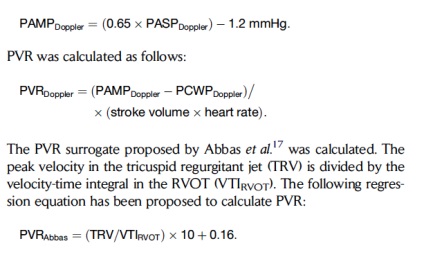

PVR lehet, például, számolni, és így

Vannak más képletek jóváhagyott különböző forgatókönyvek hemodinamikai